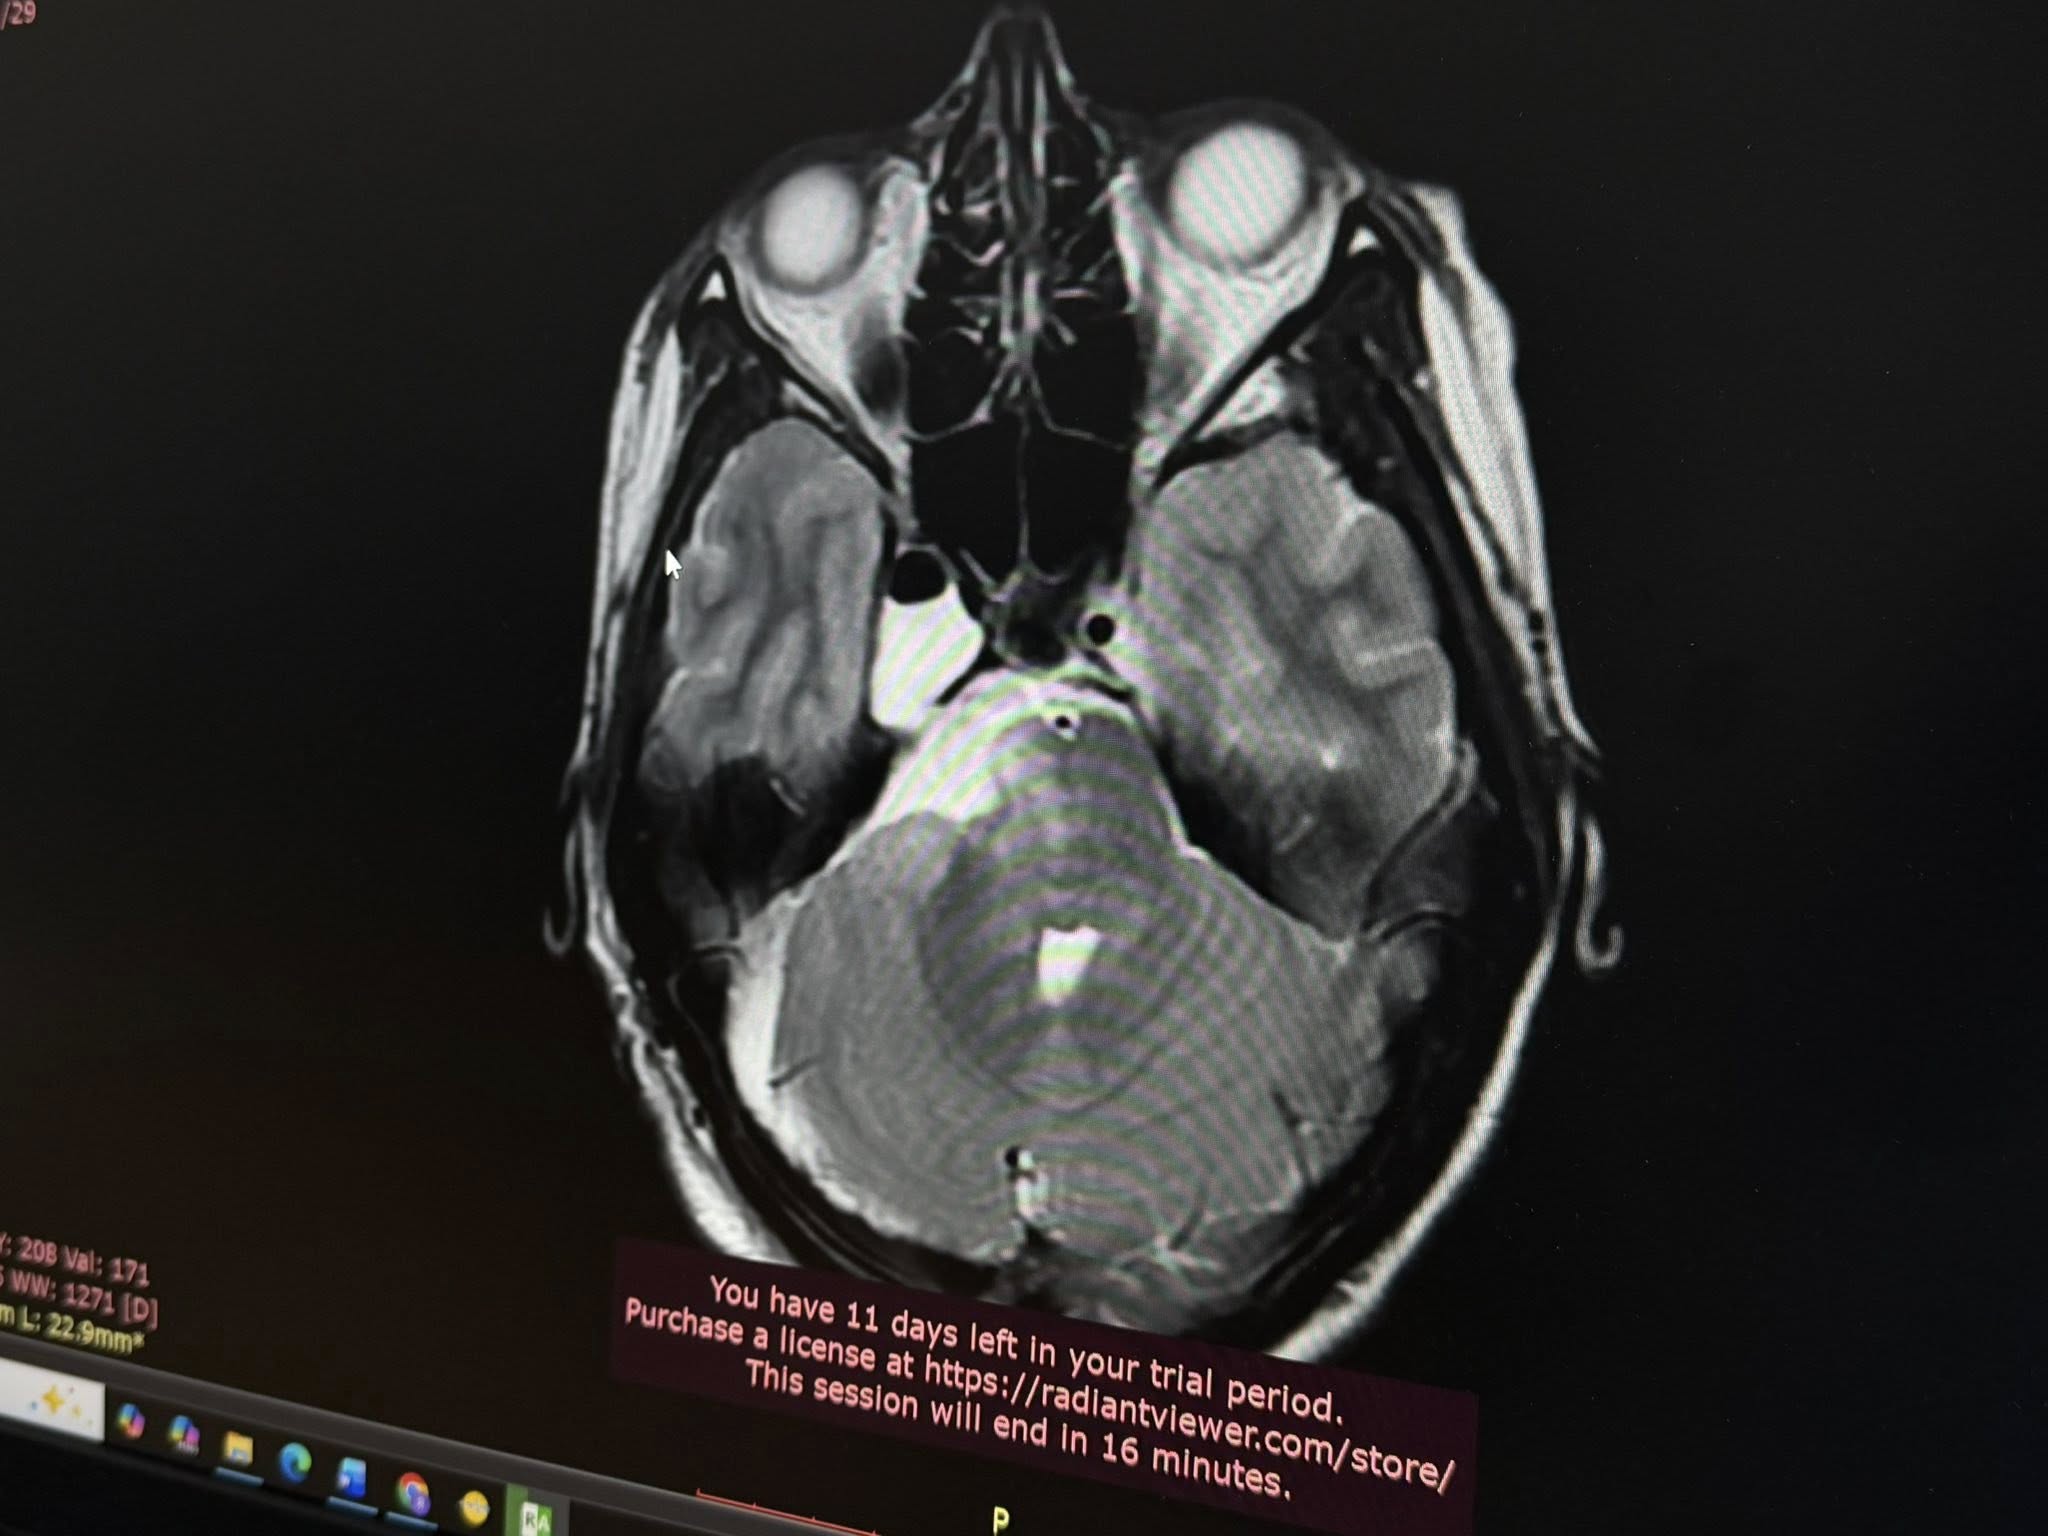

За кілька місяців стан Анастасії різко погіршився: з’явилися постійні нудота та втома, а до зниження гостроти зору додалась ще й косоокість. Крім цього, кілька разів в неї повністю зникав слух на праве вухо – і це лякало дівчину найбільше. Почались порушення координації. Тож Анастасія нарешті звернулася за допомогою. Польські спеціалісти провели МРТ і виявили у молодої українки велику пухлину головного мозку.

«Я була в шоці. Це було дуже неочікувано. Я розглядала різні варіанти, але не такий. Проте рук не опустила, зрозуміла, що потрібно шукати вихід і лікарів, яким можна довіритися», — згадує Анастасія.Довірилася своїм – львівським нейрохірургам Лікарні Святого Пантелеймона, а ті своєю чергою зіткнулися з доволі рідкісним випадком розташування пухлини. Виявилося, що у мозку Анастасії розросталася холестеатома – доброякісне новоутворення, яке зазвичай виникає у середньому вусі. Натомість у цієї пацієнтки пухлина поширилася на дві з трьох черепних ямок: на задню та середню, що є вкрай нетиповим та небезпечним.

Холестеатома виросла до загрозливих розмірів – 6 на 3 сантиметри – та вже стискала стовбур мозку, що й пояснювало проблеми зі слухом, зором та координацією. Ба більше – в задній черепній ямці також розташовані і центри дихання та серцевої діяльності, а це вже становило пряму небезпеку для життя Анастасії. Вона просто могла перестати дихати. Треба було якомога скоріше видалити пухлину, однак її локалізація значно ускладнювала цю задачу, зазначають медики.